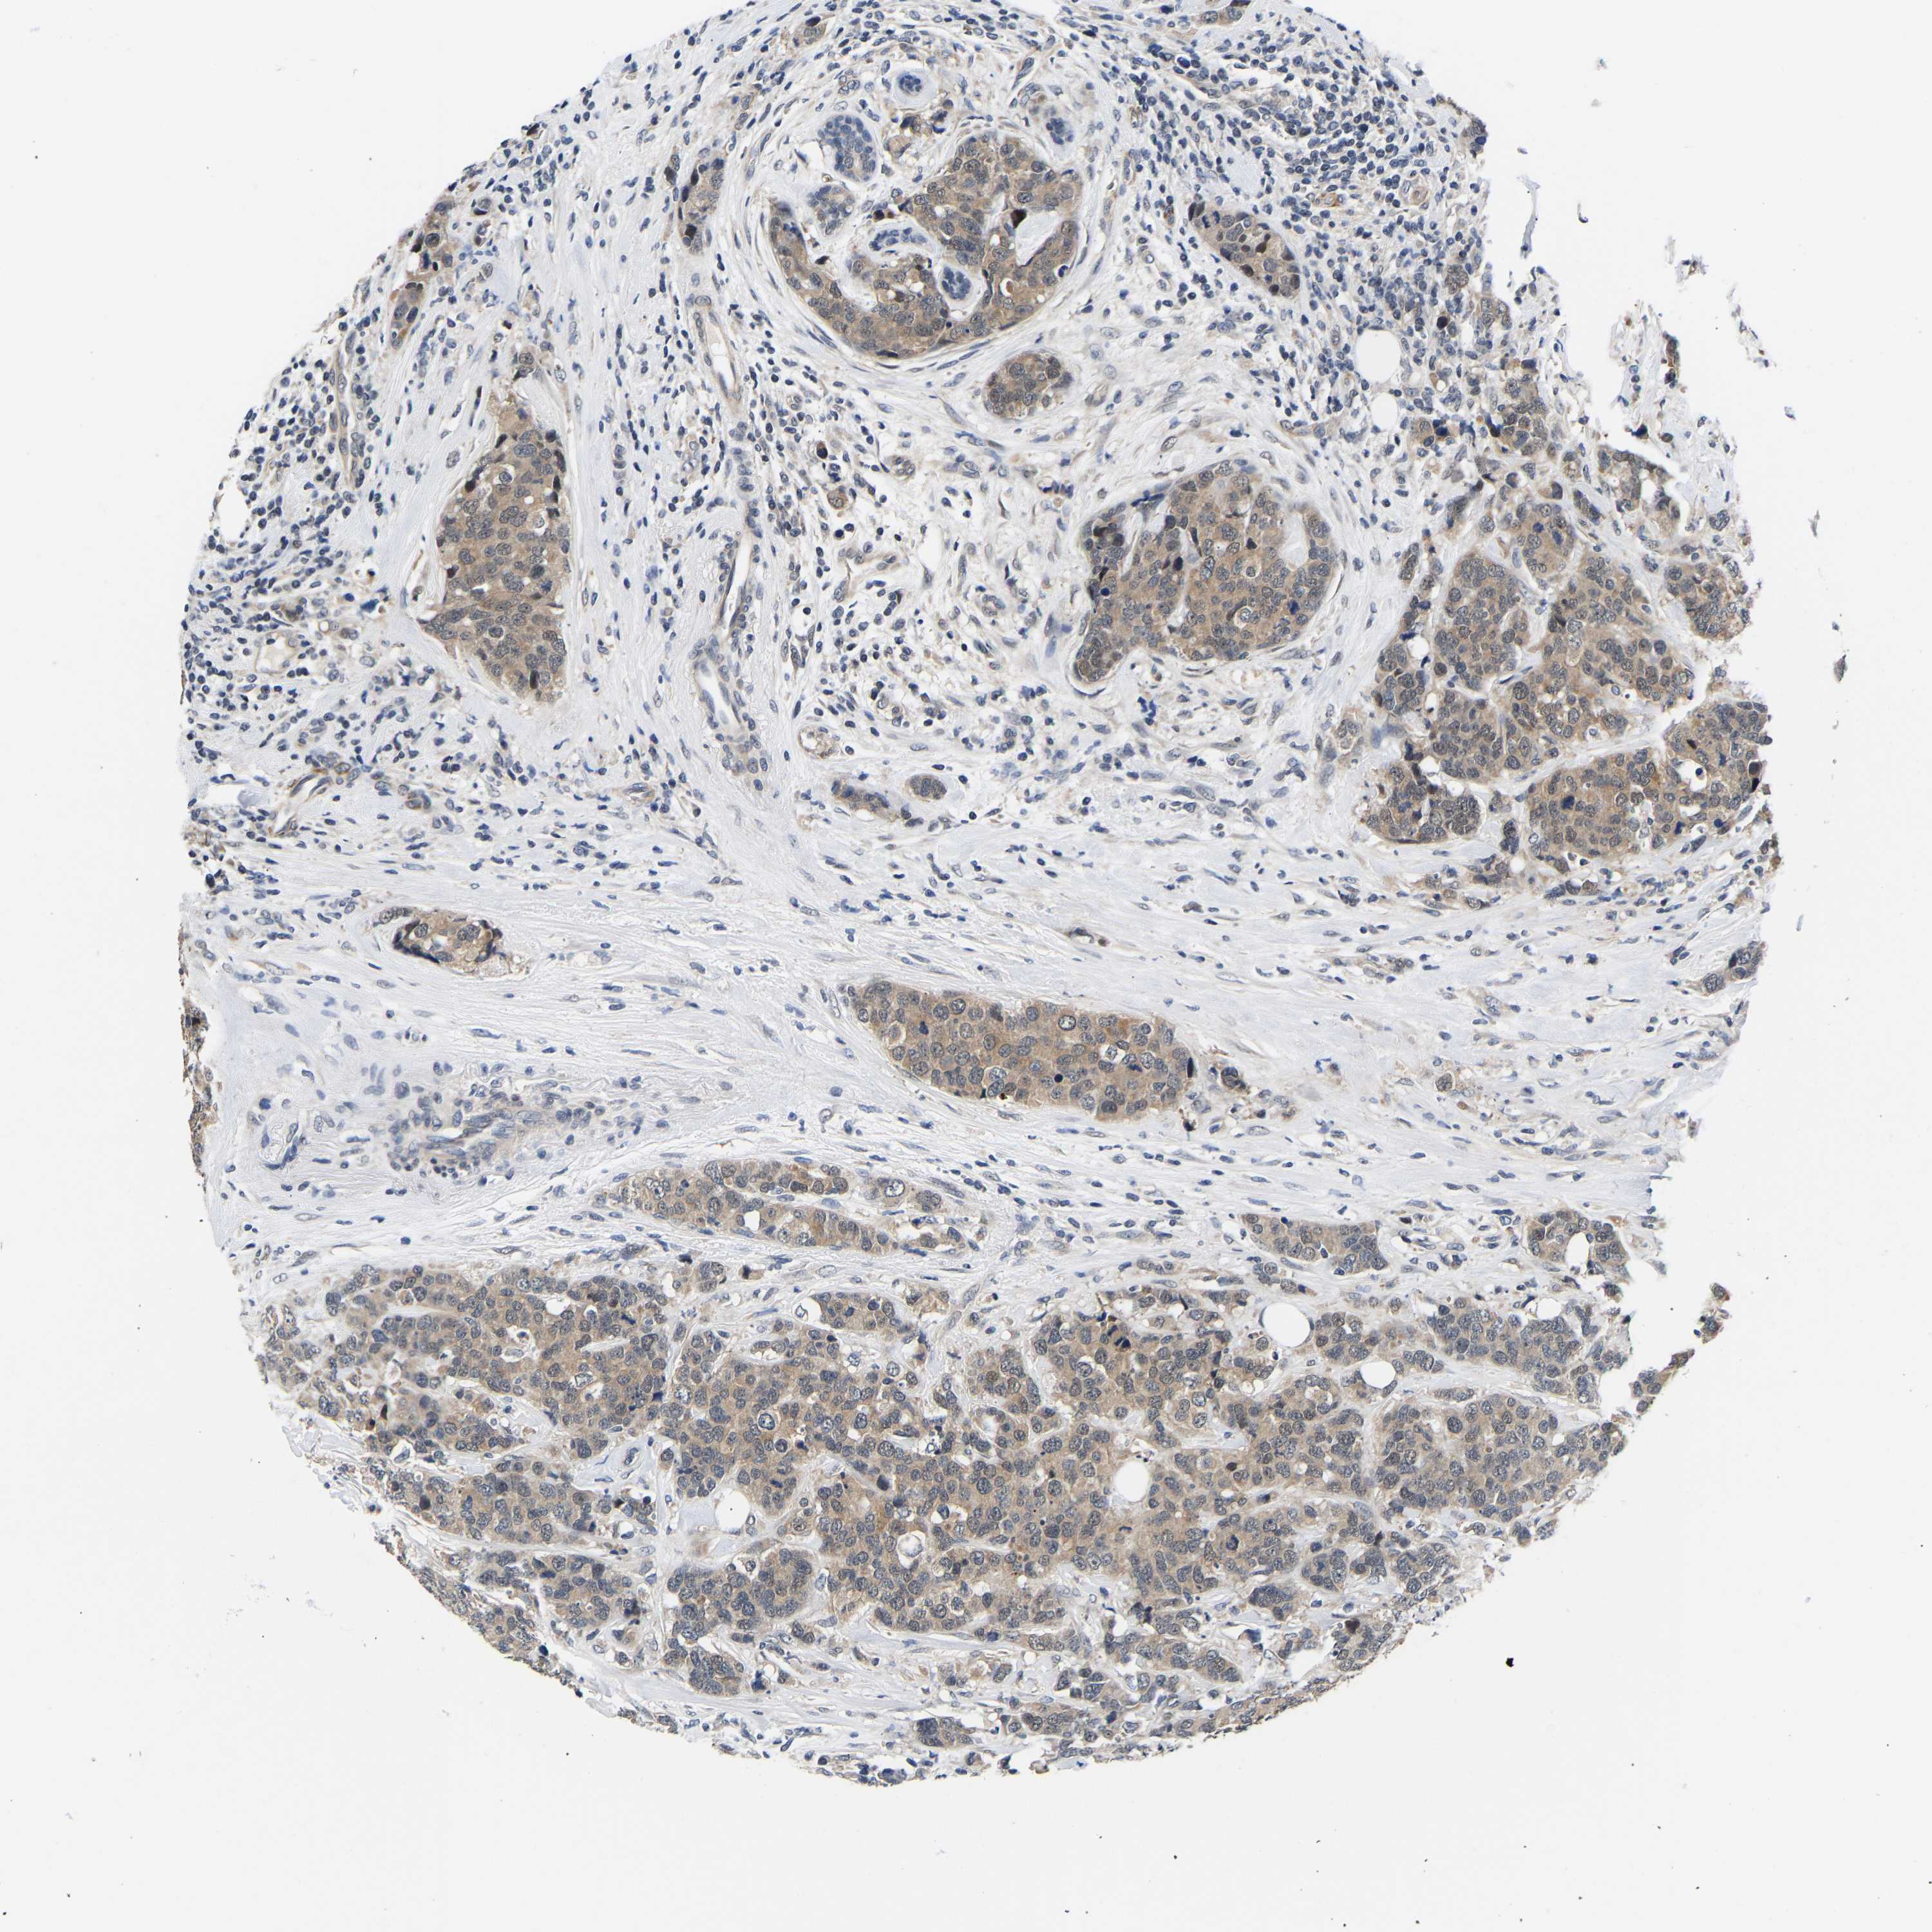

CANCER BREAST CANCER Show tissue menu

BRCA TCGA BRCA VALIDATION PROTEIN EXPRESSION